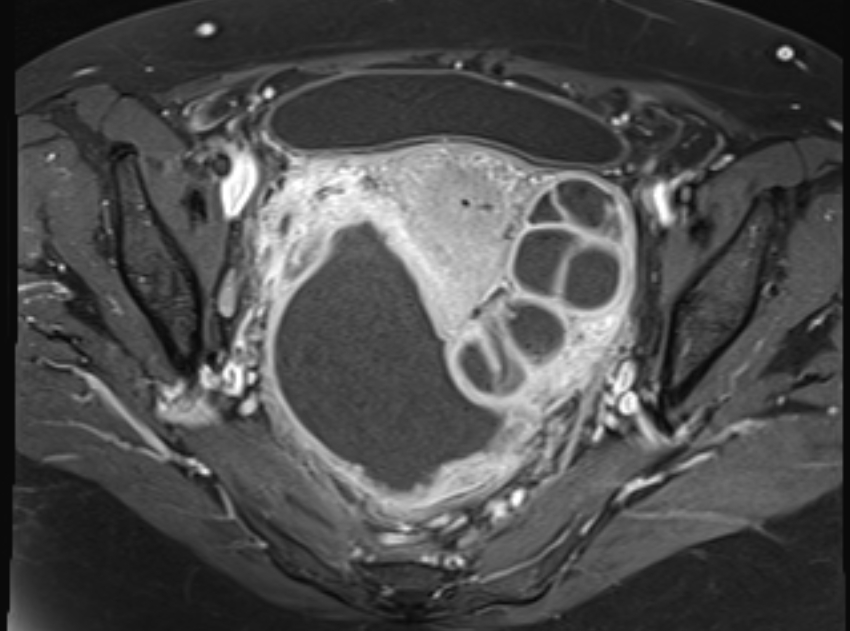

КТ-исследование абсцесса малого таза: Визуализация и диагностика

Раздел: Фотоальбом решений